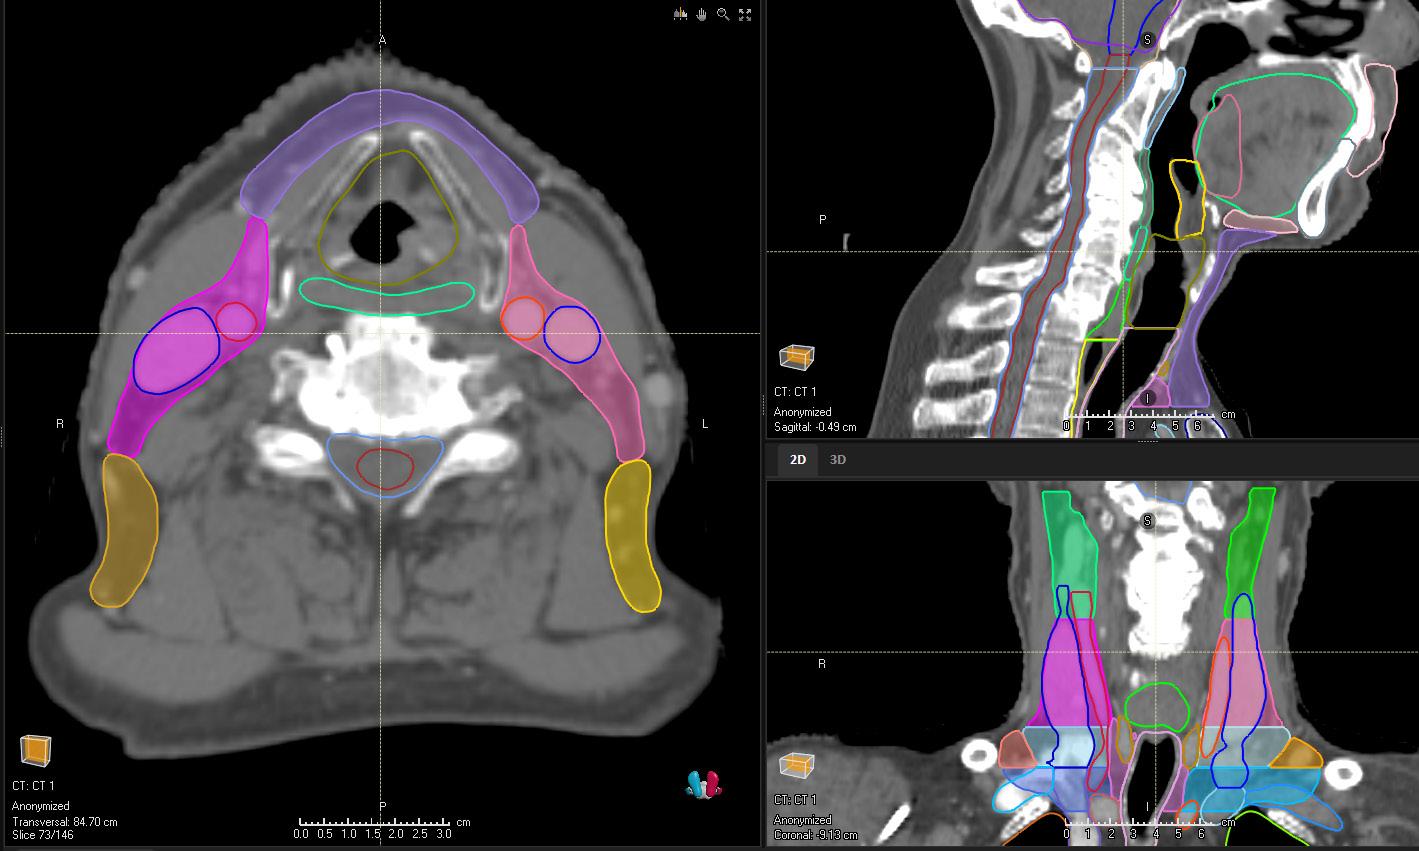

HEAD AND NECK (LYMPH NODE LEVELS) CT

STRUCTURES

LN_Neck_IA

LN_Neck _IB_L

LN_Neck _IB_R

LN_Neck _II_L

LN_Neck _II_R

LN_Neck _III_L

LN_Neck _III_R

LN_Neck _IVA_L

LN_Neck _VAB_L

LN_Neck _VAB_R

LN_Neck _VC_L

LN_Neck _VC_R

LN_Neck _VIA

LN_Neck _VIB

LN_Neck _VIIA_L

LN_Neck _VIIA_R

LN_Neck _IVA_R LN_Neck _VIIB_L

LN_Neck _IVB_L

LN_Neck _IVB_R

LN_Neck _VIIB_R